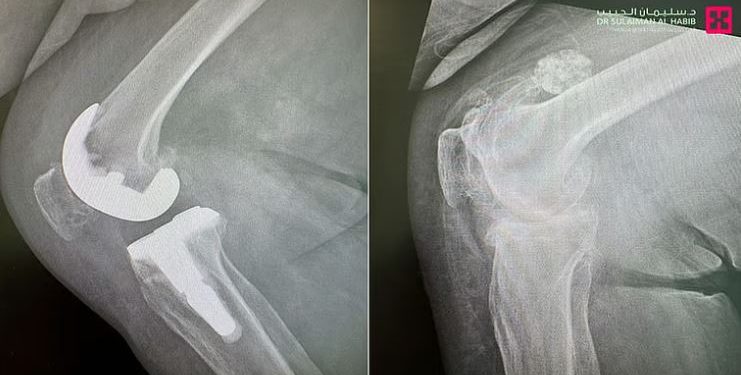

وأوضح د. سكيك أن الفريق الطبي أجرى سلسلة من الفحوصات، شملت الأشعة السينية والتصوير المتقدم، والتي كشفت عن تدهور حاد في مفصل الركبة، ما استدعى اتخاذ قرار بإجراء عملية استبدال المفصل باستخدام تقنية الروبوت الجراحي، وهي تقنية توفر دقة عالية في الزراعة، وتمنح نتائج قريبة جدًا من المفصل الطبيعي.

انطلقت العملية بتزويد النظام الروبوتي بكافة القياسات الحيوية الخاصة بالمريضة، إضافة إلى تفاصيل المفصل الصناعي المطلوب زرعه، حيث تم التخطيط الدقيق لتصحيح تقوس الساق باستخدام دعامة خاصة تعوّض عن ضعف وتصلب الأربطة. استمرت العملية 90 دقيقة تحت التخدير النصفي، وتكللت بالنجاح التام.